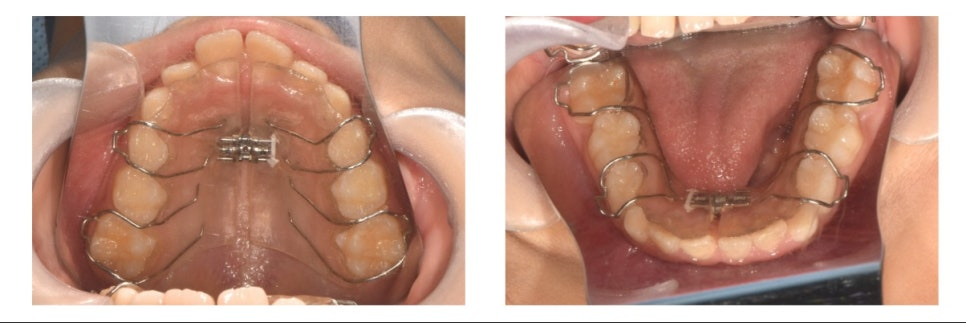

🦷 초기 치료: 공간 확보

먼저 공간을 확보하기 위해 **가철성 장치(active plate)**를 착용하였습니다.